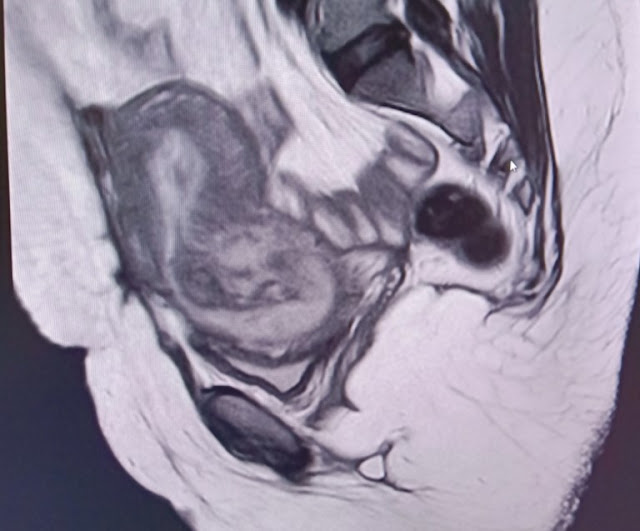

T2 images ( sag , cor &

axial) – show mixed signal fairly well defined oval shaped lesion in the low

anterior uterine segment extending into the cervix causing dilatation of the

cervix along with inferior bulge of the lower cervical lips causing effacement

of the posterior fornix of vagina with possible endocervical canal extension. Superiorly

thin extension of the T2 hypointense signal from the lesion into the

endometrial cavity was also seen. Lesion appears iso to hyperintense in T1 with

marked blooming areas within the lesion in GRE extending into the endometrial

cavity suggesting hemorrhagic contents in the lesion.

Focal grossly thinned out

anterior myometrium seen in the low uterine seg

-

ment ( LUS) showing broad

contact with the above mentioned lesion in LUS & cervix. No defect or any rupture was seen in the

uterine scar. No collection or any free fluid was seen in the parametrium.